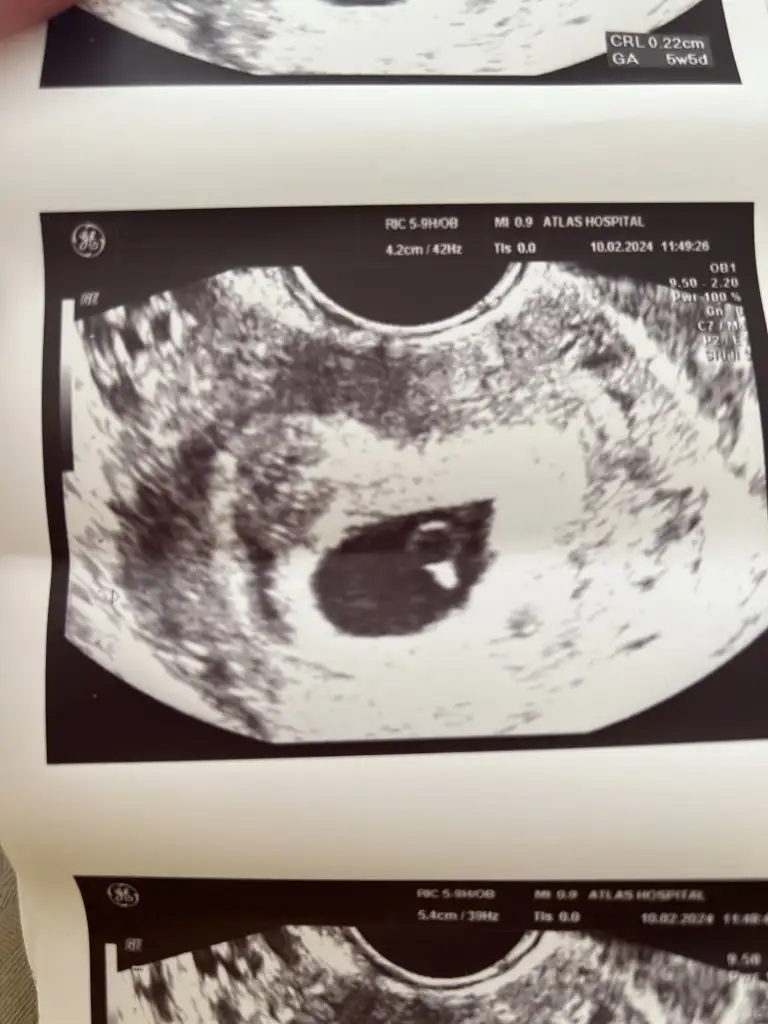

Bana da bakar mısınız vajinal ultrason

Eklentiler

• Screenshot_2023-11-12-22-15-00-033_com.miui.gallery.webp

Screenshot_2023-11-12-22-15-00-033_com.miui.gallery.webp

15,6 KB · Görüntüleme: 102